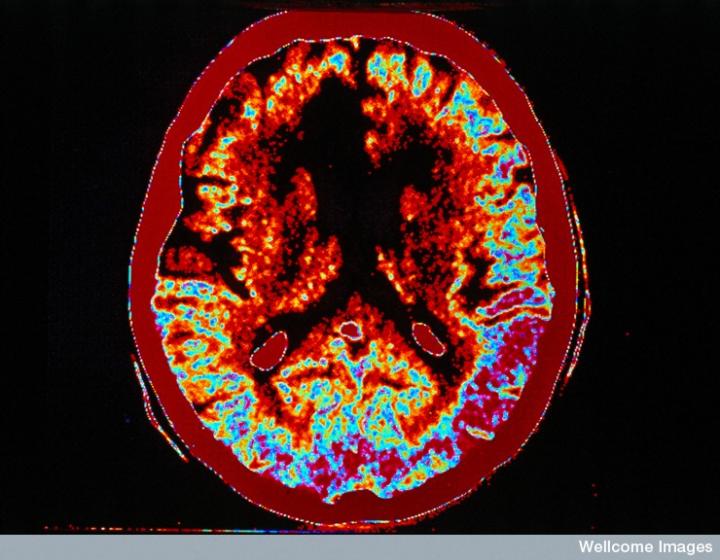

CT掃描的主圖顯示左側(cè)有一些中風(fēng)損傷,由 Wellcome Images提供。Wellcome Photo Library提供的慢性中風(fēng)的附加圖像 ,Wellcome Images,QL 從胚胎干細(xì)胞培養(yǎng)的神經(jīng)元。Ying & A. Smith, Wellcome Images 和 Yirui Sun, Wellcome Images 移植的小鼠神經(jīng)干細(xì)胞。